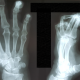

Мужчина 40 лет. Направлен на рентгенографию левой кисти , анамнеза нет и цели обследования нет.

Что за изменения в кончиках 4 и 5 пальцев ? И как описать?  Спасибо  заранее.

Пальчики разогните, вопросы пропадут)))

Думаю что это котрактура. Если задать вопрос лаборанту, то вероятнее всего, вы услышите что пальцы у пациента не разгибались

По любому, на боковой проекции ногтевые фаланги в наличии и кажутся неизменёнными. Для достоверной оценки их состояния толковый лаборант изощрится и выведет в прямой проекции (было бы желание)